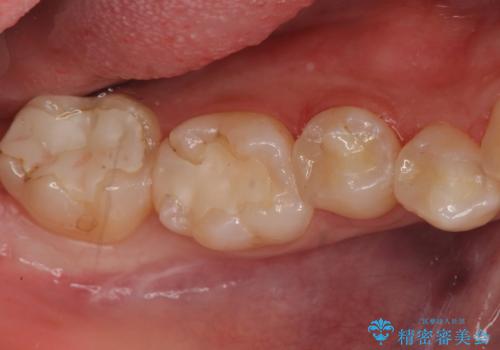

今回は虫歯の治療のみのご希望であったため、掲載している写真の右側2本(口腔内の手前側)を治療していきました。

適合がよく色も白いため、「全然違和感がないですね」と喜んでいただけました。

写真の左側2本(口腔内の奥側)は適合が悪いことが見て取れると思います。

こういった場所は汚れがたまりやすく虫歯のリスクが高くなっているため、適合の良い修復物にやりかえることをお勧めします。